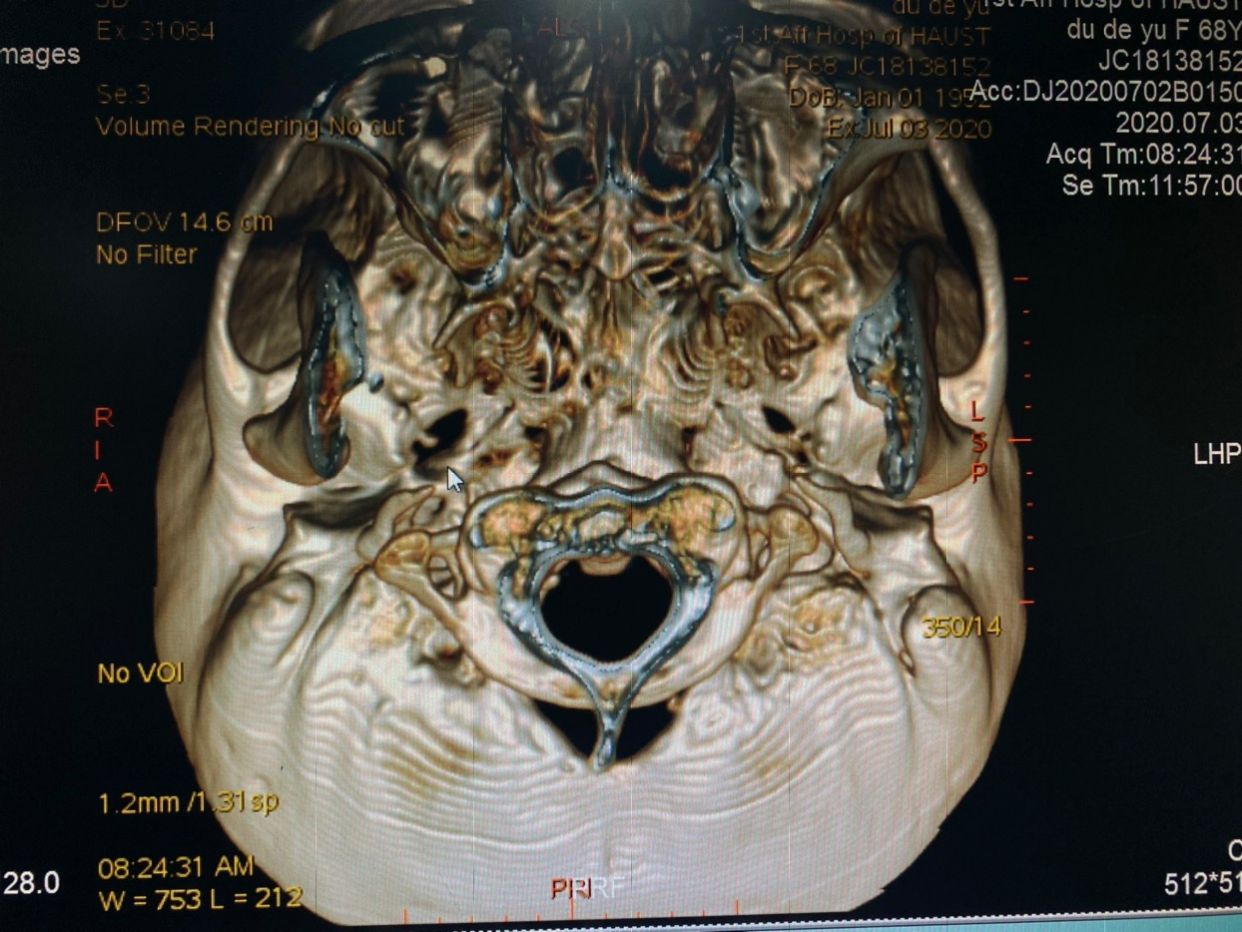

患者,女性,68岁,间断右侧颌面部疼痛40余年入院。查体:右侧V1-3支疼痛,累及右侧颞部头皮电击样疼痛。既往史:既往20年前行右侧三叉神经痛射频治疗两次,伽马刀治疗1次。术前行颅底CT检查,右侧卵圆孔破坏严重。

右侧卵圆孔内可见骨刺,增加手术难度(术中导管球囊被刺破以及进入麦氏囊腔困难)

卵圆孔与棘孔融合,如果穿刺针位置偏差,可刺破脑膜中动脉,引起出血可能。